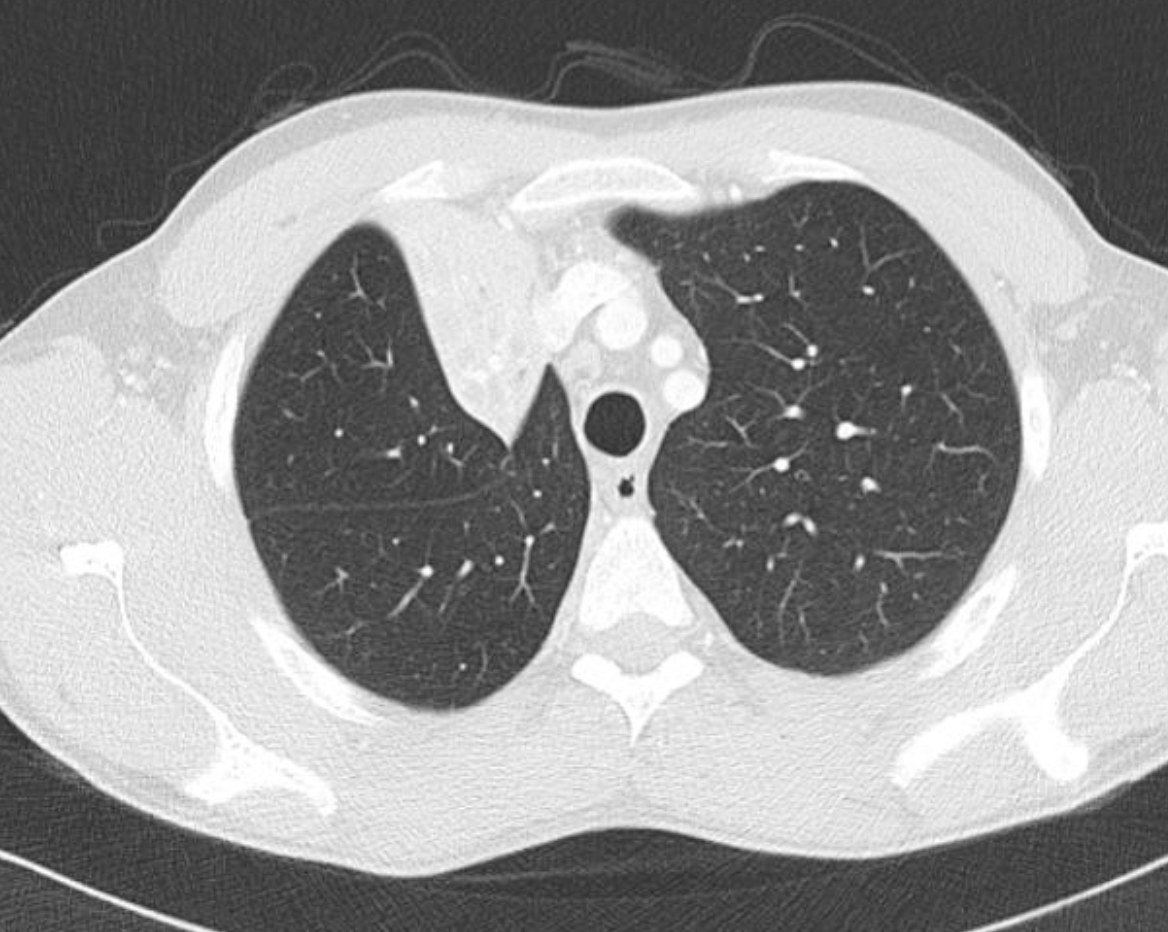

What are the features of RML collapse on CT scan

CT features: (4)

Triangular opacification abutting R heartborder, thinner at the hilum in axial image

Horizonal fissure rotates anteromedially

Oblique feature bows anteriorly

RUL rotates anterolaterally and RLL rotates posterolaterally and meets lateral to the collapsed RML